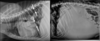

Which structures are outlined in these images?

A

white: aorta

blue arrows: caudal vena cava

11

Q

What are the characteristics of the caudal vena cava?

-maximum normal diameter is approximately the same as the aorta

-will vary in diameter with cardiac cycle and phase of respiration

-if consistently small, think hypovolemia or shock

-if consistently large, think congestive heart failure